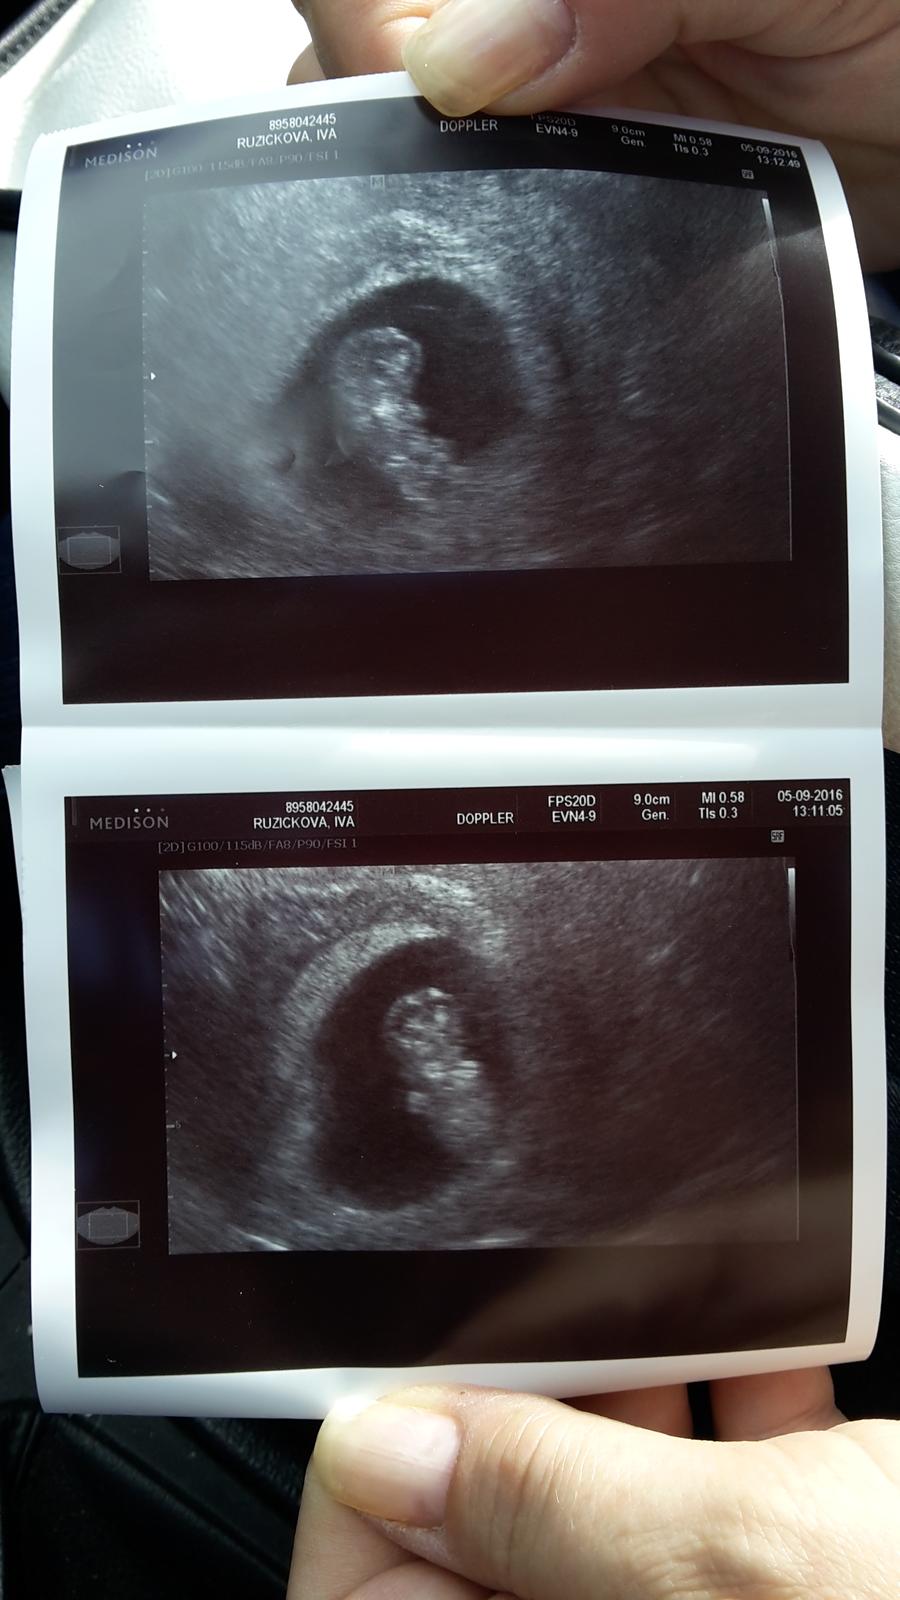

Holkyy ...brecim stestim 🙂 konecne je neco videt...a sme 9tt+3

@simazd ja sem tam pred tydnem mela flek bez rucicek a mel 2.19cm...dneska presne tyden po ma 9cm 🙂

@simazd jo a uz krasne sebou mrskal 🙂 ani doktorka nemohla zachitit srdicko poradne 🙂